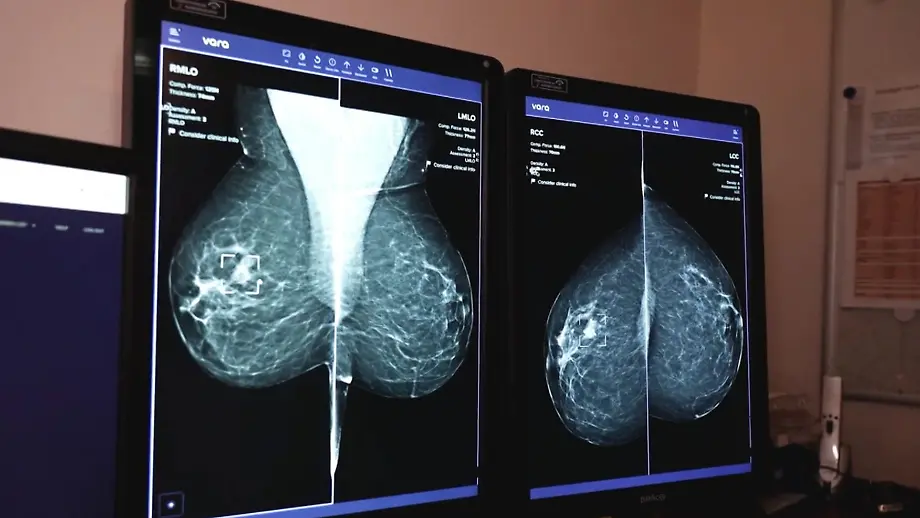

Startup MagazinVara kann per KI Brustkrebs frühzeitig erkennen

16.09.2023, 16:00 UhrKreative und innovative Geschäftsideen: Die Gründerszene gewinnt für Wirtschaft und Gesellschaft immer mehr an Bedeutung. Das "ntv Startup Magazin" beschäftigt sich diesmal mit Vara, das bei der Früherkennung von Brustkrebs hilft.